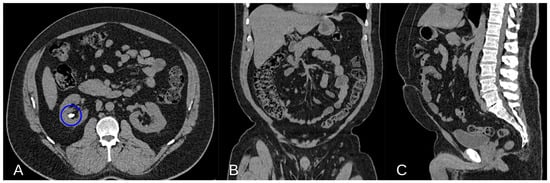

Epidemiological studies support the higher risk of kidney stone development in individuals with elevated VF, highlighting the need to consider VF not only as a risk factor for metabolic and cardiovascular diseases but also for nephrolithiasis [43] (Figure 2).

Figure 2.

Non-contrast Axial CT scan image demonstrating a calcium lithiasis in a caliceal group of the right kidney (blue circle in (A)). Non-contrast Coronal and Sagittal CT scan showing a good representation of VF ((B,C) respectively).